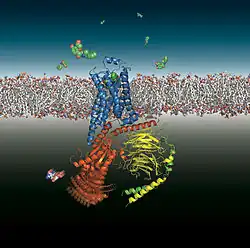

In 1986, the first gene coding for a catecholamine receptor, the β2-adrenoceptor from hamster lung, was cloned by a group of sixteen scientists, among them Robert Lefkowitz and Brian Kobilka of Duke University in Durham, North Carolina.[90] Genes for all mammalian catecholamine receptors have now been cloned, for the nine adrenoceptors α1A, α1B, α1D, α2A, α2B, α2C, β1, β2 and β3 and the five dopamine receptors D1, D2, D3, D4 and D5. Their fine structure, without agonist or agonist-activated, is being studied at high resolution.[91]

Earl Wilbur Sutherland won the 1971 Nobel Prize in Physiology or Medicine "for his discoveries concerning the mechanisms of the action of hormones", in particular the discovery of cyclic adenosine monophosphate as second messenger in the action of catecholamines at β-adrenoceptors and of glucagon at glucagon receptors, which led on to the discovery of heterotrimeric G proteins. In 1988 James Black was one of three winners of the Nobel Prize in Physiology or Medicine "for their discoveries of important principles for drug treatment", Black's "important principles" being the blockade of β-adrenoceptors and of histamine H2 receptors. In 2012, Robert Lefkowitz and Brian Kobilka shared the Nobel Prize in Chemistry "for studies of G-protein-coupled receptors".

The β2-adrenoceptor (blue) coupling to the heterotrimeric G protein GS (red, yellow, green) after binding of an agonist.

The β2-adrenoceptor (blue) coupling to the heterotrimeric G protein GS (red, yellow, green) after binding of an agonist.